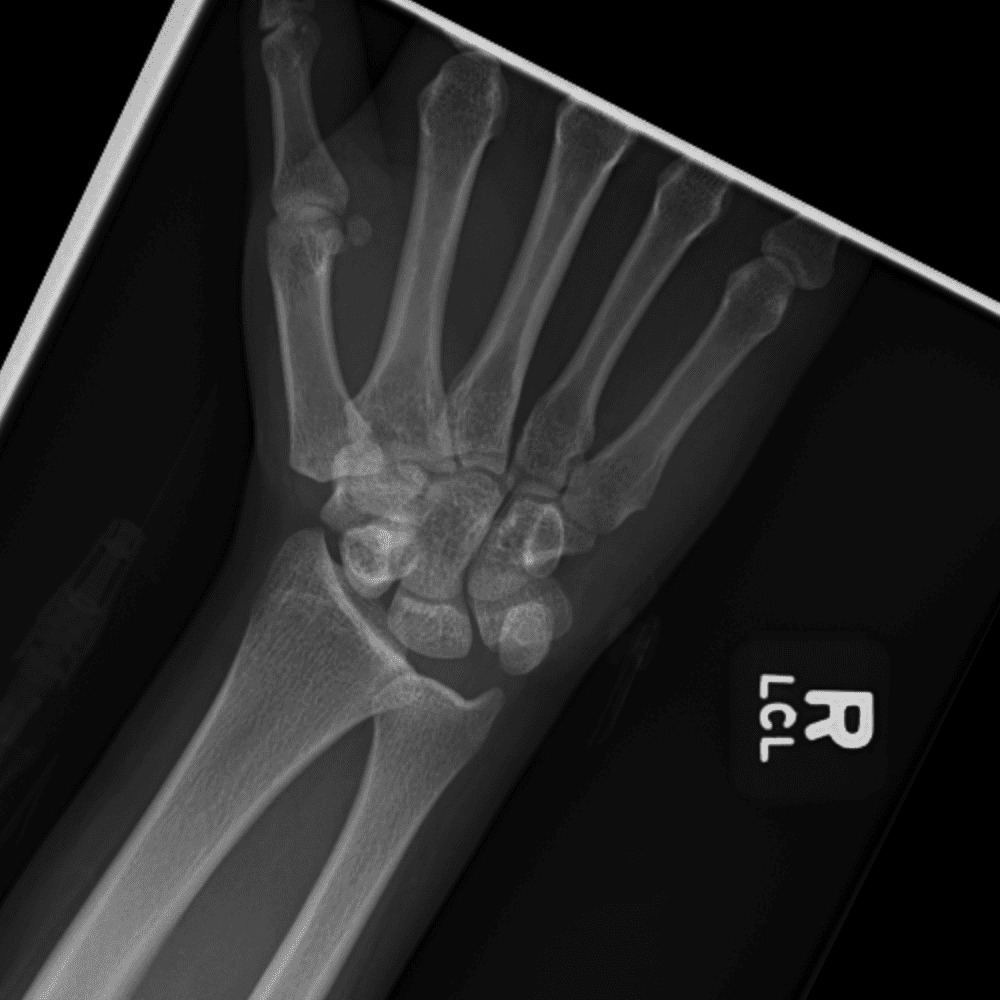

Simuliert den Dienst durch subtile oder schwierige Fälle und einige Normalbefunde.

30 Fälle